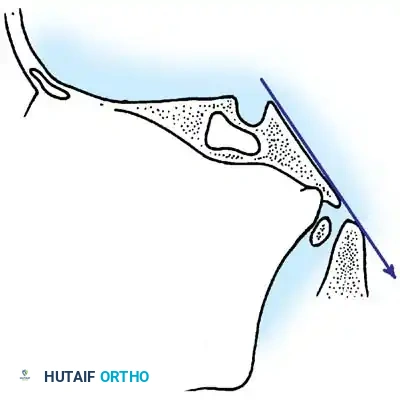

1. Wackenheim Clivus-Canal Line

This line evaluates the relationship between the cranium and the cervical canal. A line is drawn along the posterior aspect of the clivus and extended inferiorly into the cervical spinal canal. In a normal spine, this line should pass perfectly tangential to, or just posterior to, the tip of the odontoid process. Intersection with the odontoid indicates cranial settling or abnormal translation.

Fig. 37-34 Drawing of Wackenheim clivus-canal line. This line is drawn along the clivus into the cervical spinal canal and should pass just posterior to the tip of the odontoid.